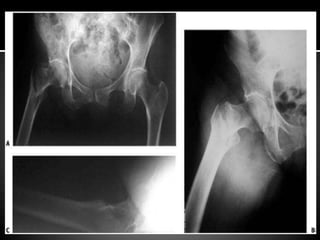

ā—¾ Pelvis with both hips –AP, xray of the

affected hip – AP and cross-table lateral